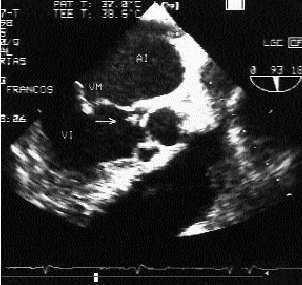

En la analítica básica sólo destacaban 8.400 leucocitos con 85% de neutrófilos y velocidad de sedimentación globular (VSG) de 43 mm. La punción del líquido cefalorraquídeo fue normal, así como la radiología de tórax y la ecografía abdominal. La tomografía axial computarizada (TAC) cerebral de urgencias fue informada como normal. A las 24 horas se apreció un paresia de la extremidad superior derecha de predominio distal. En la TAC cerebral con contraste (fig. 1) se observó una imagen hipodensa parietal izquierda. Se recibieron hemocultivos y urinocultivos positivos para S. aureus. En el ecocardiograma (EcoCG) transesofágico (fig. 2) se apreció una válvula aórtica trivalva, con el velo no coronario redundante en forma de cuenco en diástole y por debajo una imagen vibrátil de 3 mm en el tracto de salida del ventrículo izquierdo, sospechoso de «verruga» e insuficiencia valvular leve. La resonancia magnética (RM) cerebral (fig. 3) mostró múltiples lesiones nodulares supratentoriales, bihemisféricas, más numerosas en el lóbulo frontal izquierdo, con un tamaño desde algunos milímetros a 2 centímetros, captando contraste y sin existir efecto masa. En la evolución del paciente, que se hallaba asintomático desde el punto de vista cardiológico, fue apareciendo progresivamente un soplo pandias tólico aórtico y otro sistólico mitral. Evolutivamente fue desapareciendo la fiebre, la sintomatología general y la parésica, así como las imágenes lesionales en TAC y RM, con el tratamiento antibiótico. Se efectuó el diagnóstico de endocarditis infecciosa por S. aureus, abscesos cerebrales múltiples y valvulopatía aortomitral.

Fig. 2. Ecocardiograma transesofágico.